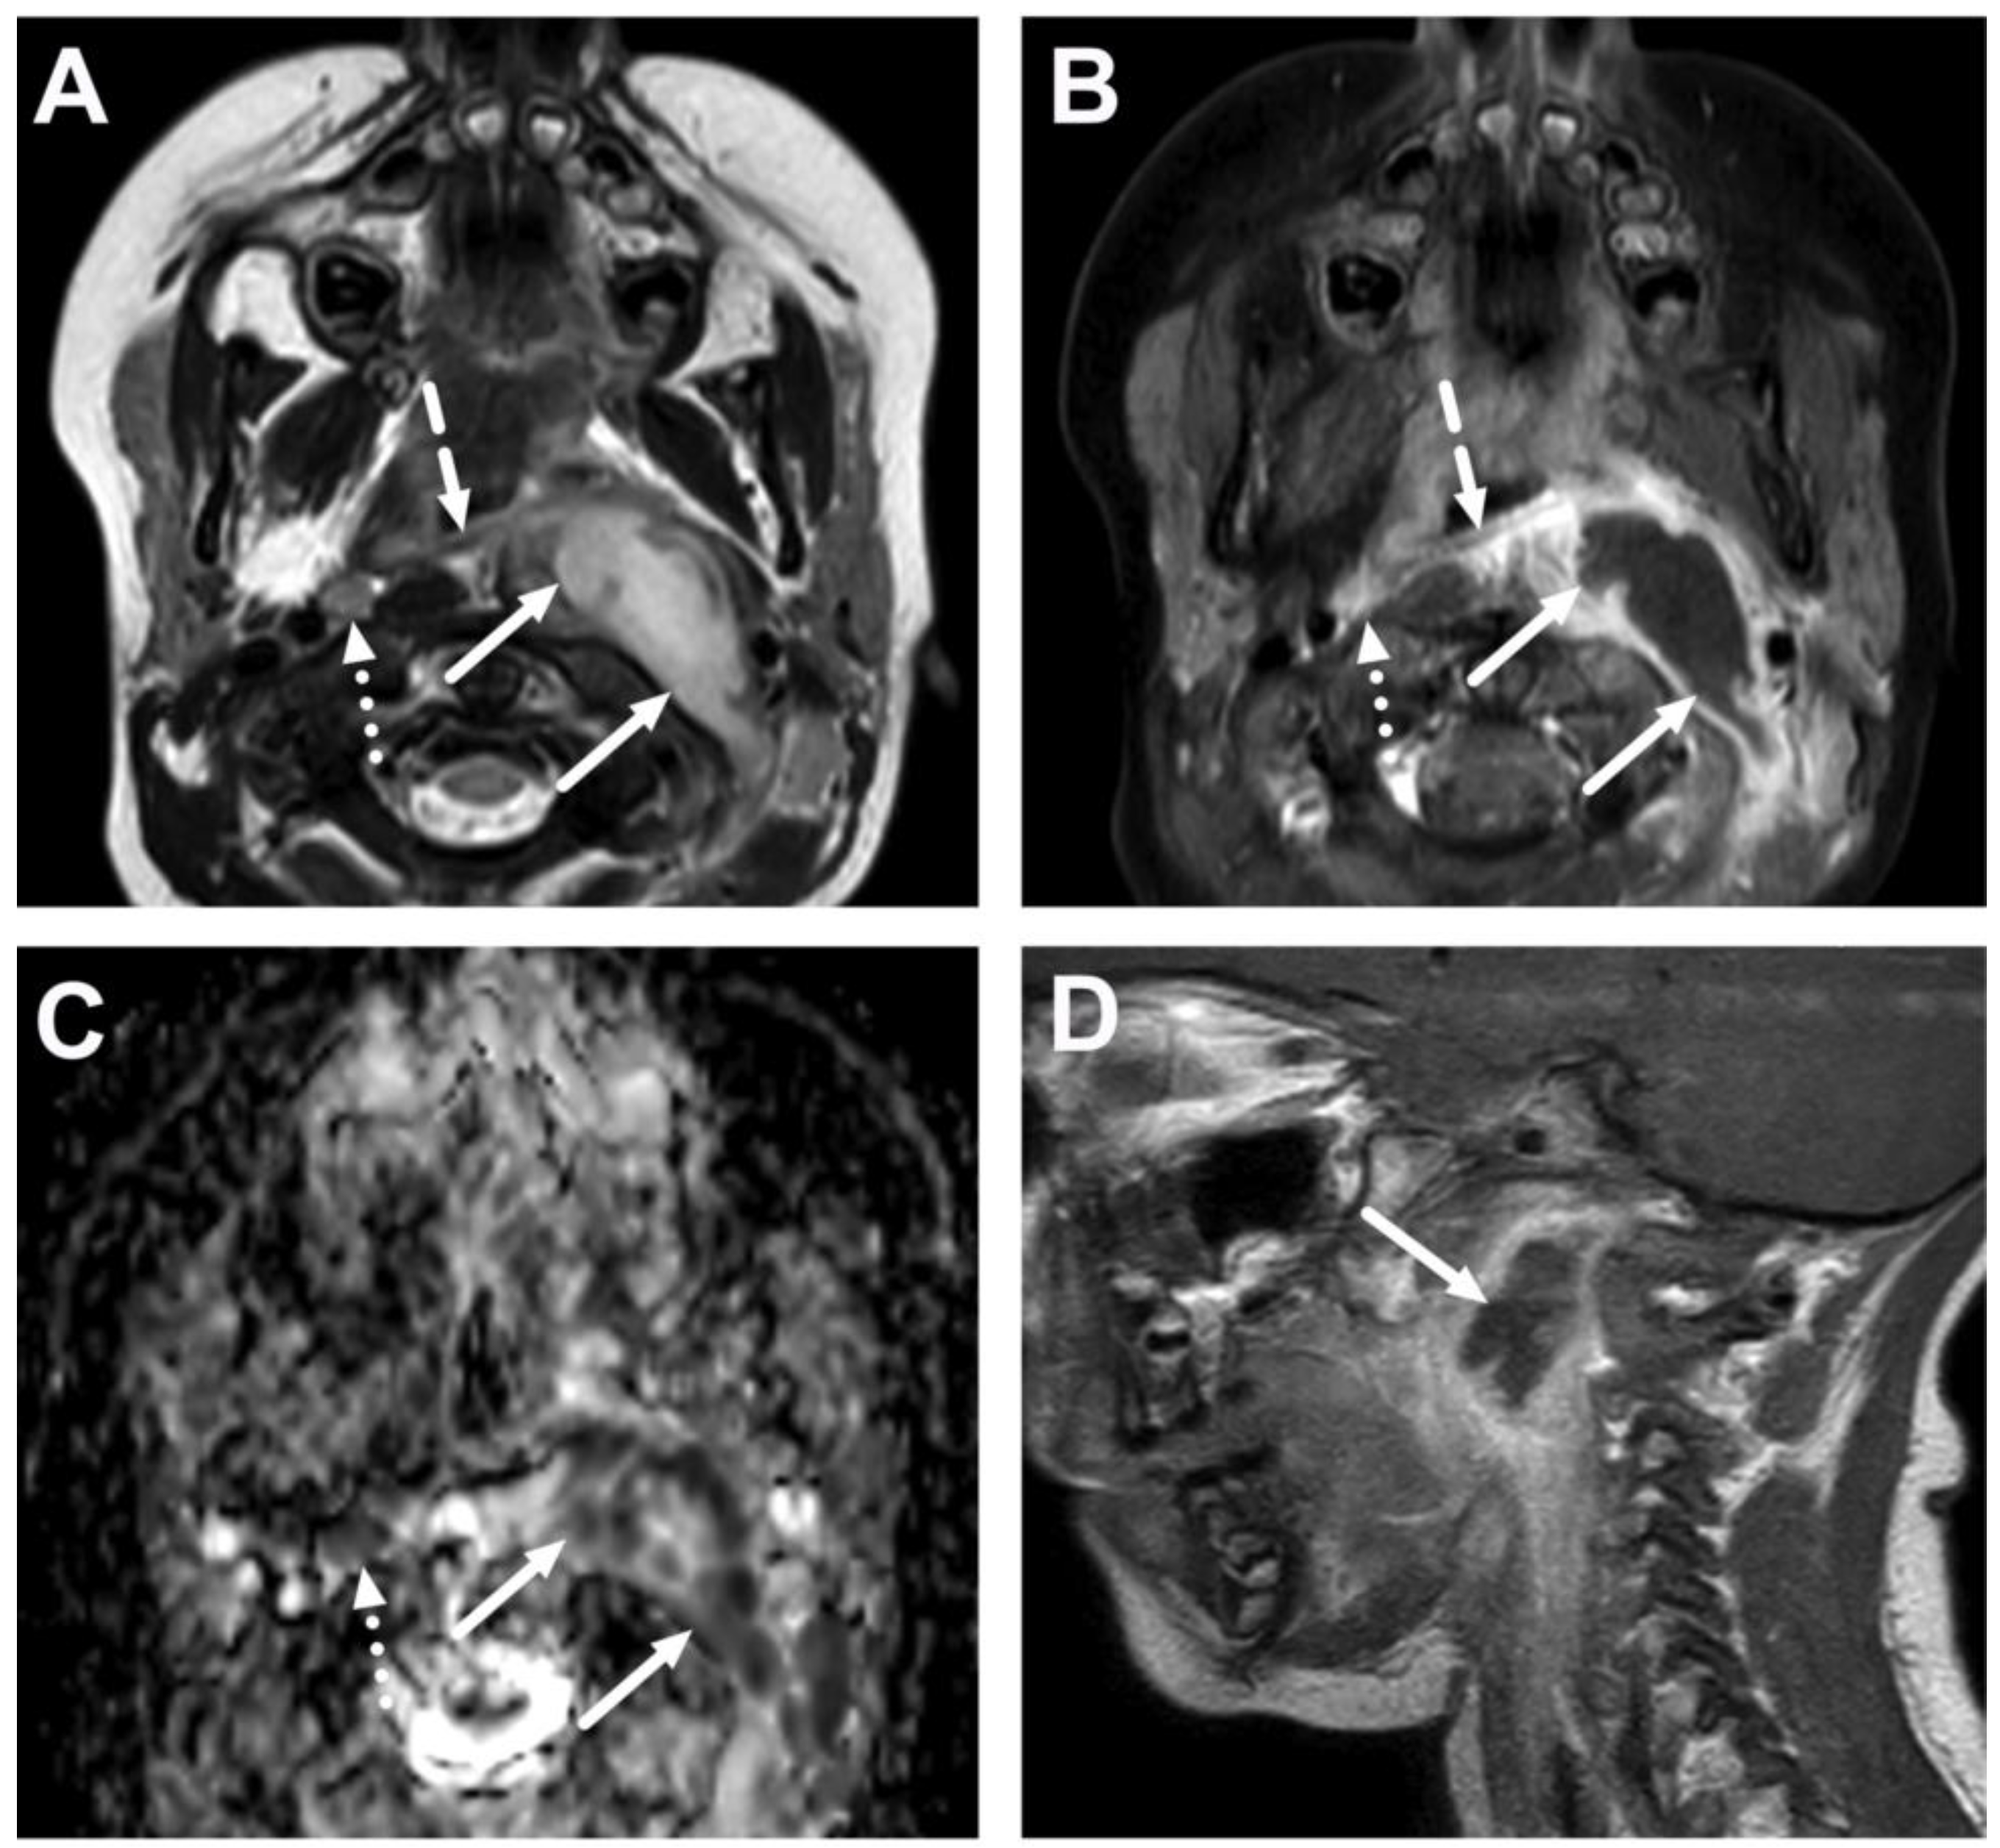

4.2. Retropharyngeal Abscesses and Suppurative Lymphadenitis

| Abscess | T1 SE T2 Dixon (water) DWI post-contrast T1 Dixon (water) | Non-enhancing collection with low ADC values enclosed in abnormally enhancing soft tissue edema. | Detection of an abscess usually requires operative consideration and exact abscess location, and extensions are useful in operative planning. | Abscesses may have an intermediate T2 signal content; blood products and/or postoperative status may complicate abscess assessment; necrotic lymph nodes may be misinterpreted as suppurative lymphadenitis. |